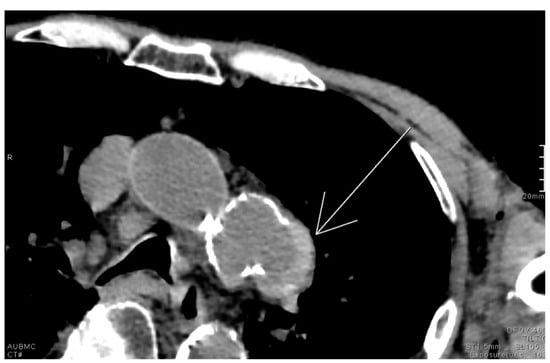

Cosmic Signs in Radiology: A Pictorial Review

Pattern recognition remains a cornerstone of radiologic interpretation, as it facilitates a confident and comprehensive differential diagnosis. Certain pathologies present with specific and highly recognizable patterns on imaging modalities. These patterns can resemble familiar real-life phenomena, including cosmic bodies that surround us. We present in this article a compilation of radiologic signs across various modalities that take inspiration from cosmic phenomena. For each sign, we summarize its defining imaging appearance, typical clinical context, and common pitfalls; where available, we note diagnostic performance (e.g., sensitivity/specificity) to guide appropriate weighting in practice. By coupling memorable imagery with succinct clinical guidance, this pictorial review aims to support a faster, more accurate pattern recognition that is applicable in both low-resource and tertiary care settings, while recognizing that these signs function as educational aids rather than validated diagnostic tests. In familiarizing themselves with these classic signs, training radiologists can benefit from an engaging and memorable way of recognizing various pathological conditions. Full article

Figure 1